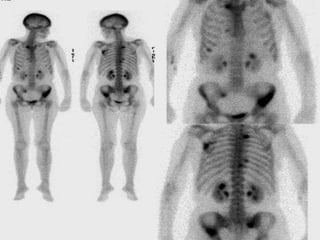

• 44.

STAGING • Based uponthis initial evaluation, most patients require additional imaging. This may include whole body positron emission tomography (PET), integratedCT/PET, bone scanning, magnetic resonance imaging (MRI) of the chest wall or brain, and/or CT of the brain.

• 45.

• Staging forNSCLC : TNM classification • Staging of SCLC uses the Veterans Administration Lung Study Group designations of limited (confined to one hemithorax) or extensive (beyond one hemithorax)